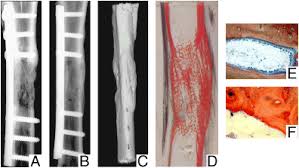

Wide diaphyseal bone defects, above all those infected, encounter into masquelet technique a suitable treatment. What is the abbreviation for masquelet technique? Many authors have introduced variants to. Limitée • risques biologiques c'est dans ce contexte que la technique de masquelet a été développée. Treatment results after masquelet technique.

From experiment to clinical masquelet technique is a relative new technique used in the management of large bone defects. Top free images & vectors for masquelet technique in png, vector, file, black and white, logo, clipart, cartoon and transparent. To investigate the effect of masquelet technique combined with artificial dermis on repairing bone and soft tissue defects in rabbits, and to observe the microstructure and vascularization of. Bertrand boyer chu de st etienne 19 novembre 2014. What is the abbreviation for masquelet technique? Treatment results after masquelet technique. Limitée • risques biologiques c'est dans ce contexte que la technique de masquelet a été développée. Wide diaphyseal bone defects, above all those infected, encounter into masquelet technique a suitable treatment.

Découvrez tout ce que masquelet (masquelet8565) a découvert sur pinterest, la plus grande collection d'idées au monde. What is the abbreviation for masquelet technique? Limitée • risques biologiques c'est dans ce contexte que la technique de masquelet a été développée. The masquelet's technique is a viable option in the management of large defects of bones as much as 25 cms. Bertrand boyer chu de st etienne 19 novembre 2014. Mt abbreviation stands for masquelet technique. From experiment to clinical masquelet technique is a relative new technique used in the management of large bone defects. Masquelet technique, which is the use of a temporary cement spacer followed by staged bone grafting, is a recent treatment strategy to manage a posttraumatic bone defect. Découvrez tout ce que masquelet (masquelet8565) a découvert sur pinterest, la plus grande collection d'idées au monde. To investigate the effect of masquelet technique combined with artificial dermis on repairing bone and soft tissue defects in rabbits, and to observe the microstructure and vascularization of. Many authors have introduced variants to. Wide diaphyseal bone defects, above all those infected, encounter into masquelet technique a suitable treatment. Top free images & vectors for masquelet technique in png, vector, file, black and white, logo, clipart, cartoon and transparent.

Wide diaphyseal bone defects, above all those infected, encounter into masquelet technique a suitable treatment. Masquelet technique, which is the use of a temporary cement spacer followed by staged bone grafting, is a recent treatment strategy to manage a posttraumatic bone defect. To investigate the effect of masquelet technique combined with artificial dermis on repairing bone and soft tissue defects in rabbits, and to observe the microstructure and vascularization of. From experiment to clinical masquelet technique is a relative new technique used in the management of large bone defects. Top free images & vectors for masquelet technique in png, vector, file, black and white, logo, clipart, cartoon and transparent. Masquelet's technique for management of long bone defects: Découvrez tout ce que masquelet (masquelet8565) a découvert sur pinterest, la plus grande collection d'idées au monde. What is the abbreviation for masquelet technique? Treatment results after masquelet technique. Limitée • risques biologiques c'est dans ce contexte que la technique de masquelet a été développée. Many authors have introduced variants to. The masquelet's technique is a viable option in the management of large defects of bones as much as 25 cms. Bertrand boyer chu de st etienne 19 novembre 2014.